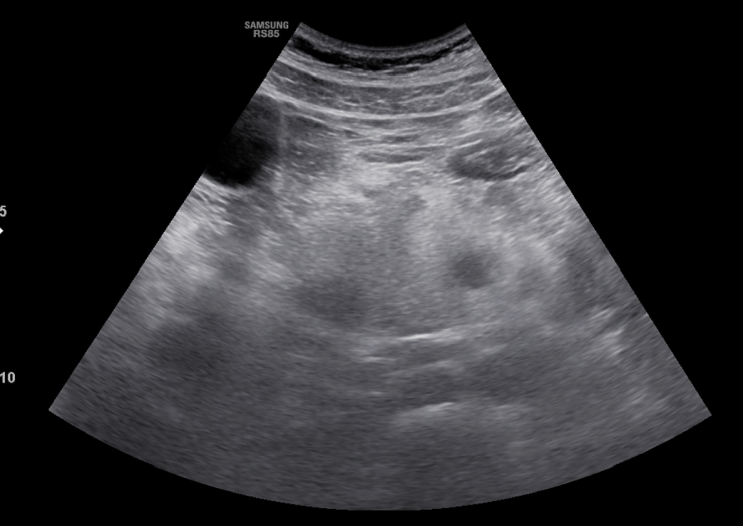

[신당동 소화기진료]서울으뜸내과, 복통으로 진단된 췌장염(복부초음파)

#서울으뜸내과 #급성췌장염 #급성췌장염의원인 #복부초음파 #신당동소화기진료 #왕십리소화기진료 #상왕십...